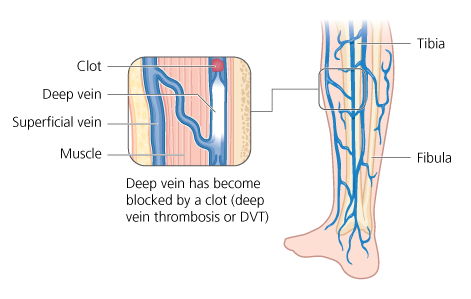

Gastrocnemius Vein Dvt

deep vein knee replacement pain blood thrombosis leg veins surgery clots dvt clot total calf may hip foot body common

deep vein veins thrombosis leg

Deep vein thrombosis. Vein thrombosis dvt pathophysiology limb rcemlearning rarely typically occur. Venous anatomy thrombosis superficial veins deep health sources trusted